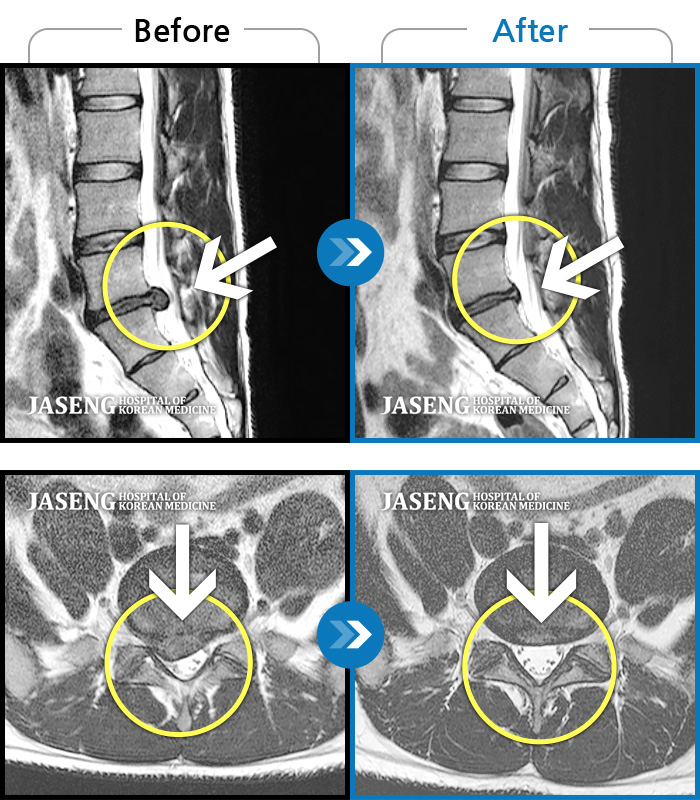

Before

After

환자에게 사전 동의를 받아 동일 조건에서 촬영되었습니다.

개인에 따라 치료 후 부작용이 발생할 수 있으니 의료진과 상담 후 치료를 진행하시기 바랍니다.

허리, 우측 엉치, 우측 허벅지 전면, 무릎 통증

허리 통증 및 오른쪽 발목의 근력저하